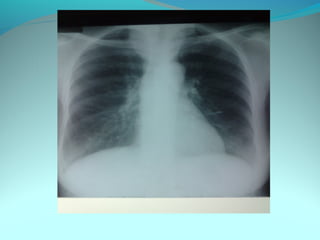

Image radiologique bilaterale

A droite : clarté sous claviculaire et axilaire droite arrondie de 3 cm de

diam entourée d une paroi de 4mm d’épaisseur

Le 1/3 sup du poumon droit est le siege d’opacité nodulaire avec

quelque clarté

A gauche: le 1/3 moyen est le siege d’opacité nodulaire et de clarté de

taille variable

DIAGNOSTIC:

Tuberculose pulmonaire bilaterale cavitaire